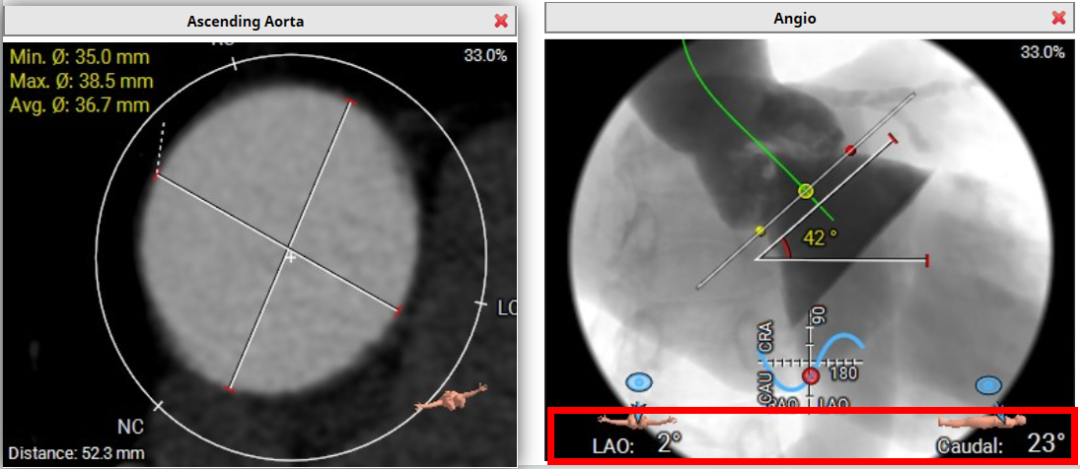

升主动脉直径36.7mm; 主动脉夹角: 42°

23mm Circle 法评估:

20mm Circle 法评估:

外周血管入路评估:右侧股动脉最小直径:5.9mm,左侧股动脉最小直径:5.7mm;无钙化。